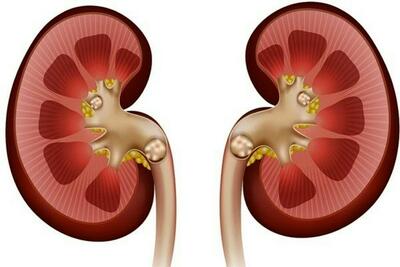

نارسایی کلیه

رابطه مصرف مسکن در بیماران میگرنی و آسیب به کلیه

یک جراح کلیه و پروستات با اشاره به پیشگیری و درمان بیماریهای کلیوی توضیحاتی ارائه کرد.

عدم کنترل قند خون موجب نارسایی کلیه

فوق تخصص کلیه دانشگاه علوم پزشکی بابل عدم کنترل قند خون را موجب نارسایی کلیه دانست.

راه های محافظت از سلامت کلیه ها

رکنا: سلامت کلیه ها بسیار مهم است.

اهمیت تستهای سالانه عملکرد کلیوی از ۴۰ سالگی به بعد

نارسایی مزمن کلیه یک بیماری خاموش است که فرد مبتلا ممکن است سالها از آن بیاطلاع باشد؛ علل ایجاد کننده این بیماری، اغلب به بیماریهای دیابت و فشار خون بالا بازمیگردد.